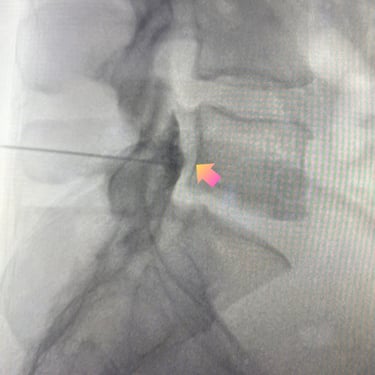

La discopatía lumbar y la espondiloartrosis forman parte del proceso degenerativo de la columna vertebral y pueden generar dolor lumbar persistente, irradiación hacia miembros inferiores y limitación funcional. Diversos estudios clínicos han demostrado que el bloqueo lumbar selectivo es una herramienta diagnóstica y terapéutica útil en estos pacientes. El procedimiento consiste en la infiltración guiada por fluoroscopía o ecografía de anestésicos locales y corticoides cerca de la raíz nerviosa o articulación facetaria comprometida. Esta técnica permite confirmar la fuente del dolor y disminuir la inflamación neural. En pacientes seleccionados, puede mejorar significativamente la calidad de vida y retrasar o evitar tratamientos quirúrgicos.